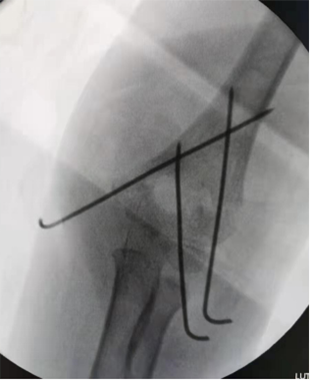

肱骨外髁骨折闭合复位克氏针内固定术